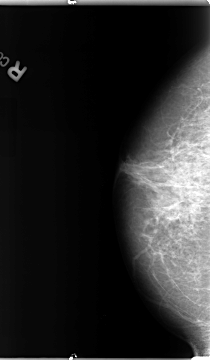

B_3094_1.RIGHT_MLO

RIGHT_CC LINES 4680 PIXELS_PER_LINE 2728 BITS_PER_PIXEL 12 RESOLUTION 50 NON_OVERLAY

RIGHT_MLO LINES 4664 PIXELS_PER_LINE 2568 BITS_PER_PIXEL 12 RESOLUTION 50 NON_OVERLAY